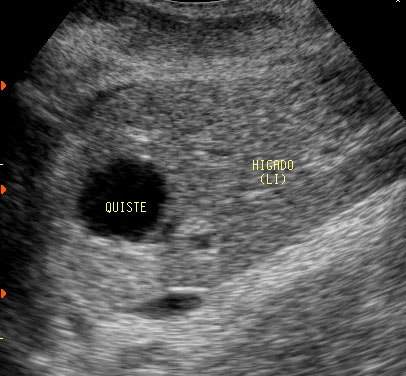

Masas abdominales

Quistes ovaricos